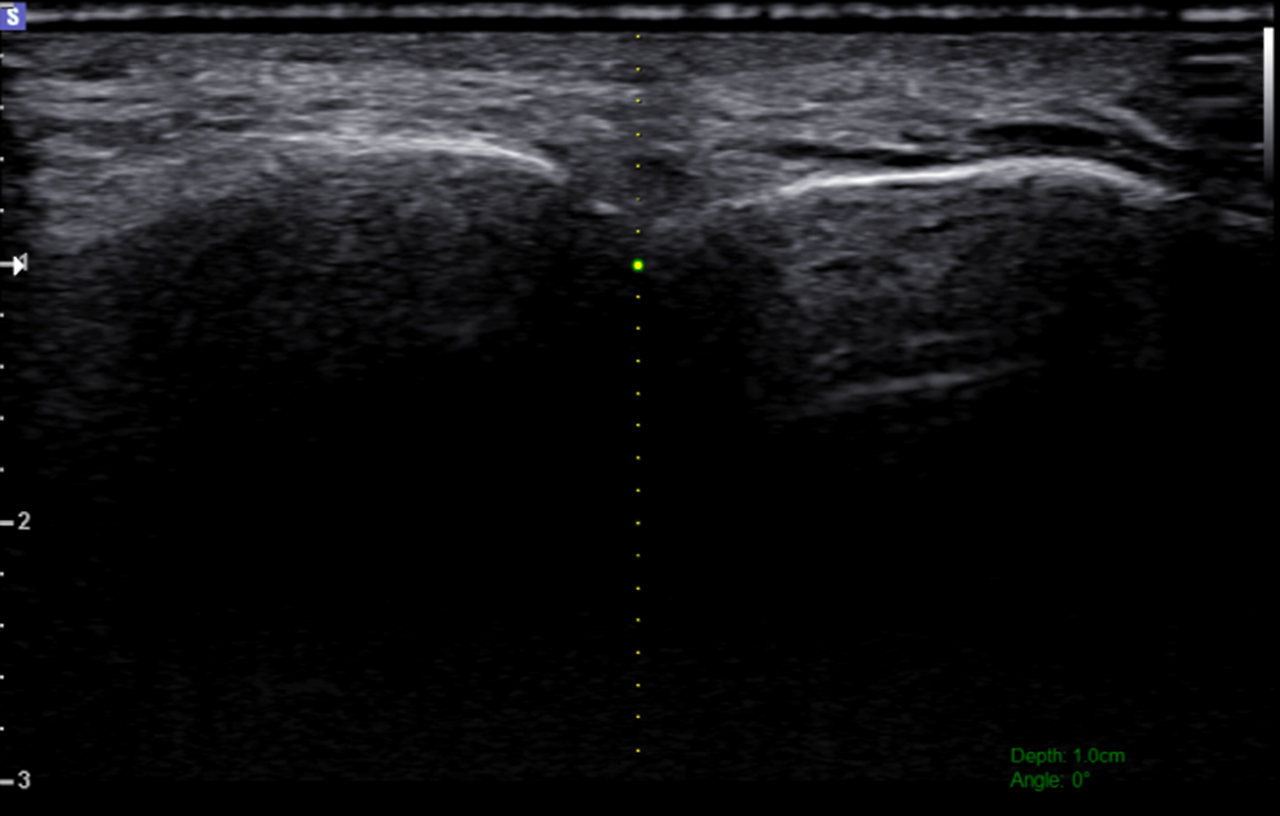

그림11.png 촬영 일시: 2025.07.01

<Fig 2. SI(초음파유도하)주사치료 진행 영상>

SI 치료는 초음파로 정확한 위치를 확인하면서

3차신경 부위에 직접 약물을 주입하는 치료법이에요.

기존의 먹는 약만으로는 한계가 있을 때

효과적으로 신경의 염증을 가라앉히고

압박을 줄여주는 치료죠.